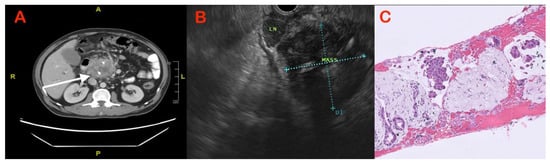

| In patients with underlying CP who develop a malignancy, the mass displaces the calcifications to the periphery. |